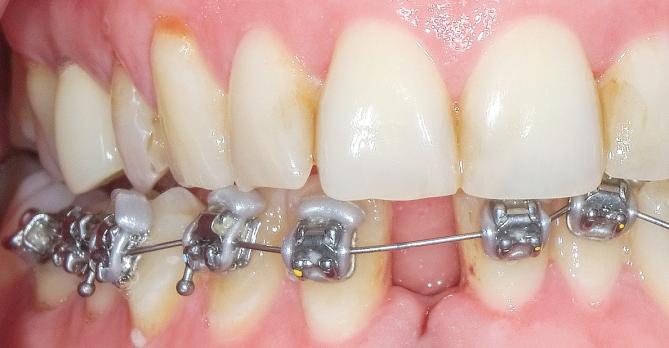

Voor het stellen van een orthodontische diagnose is het essentieel om systematisch gegevens te verzamelen uit het extra- en intraorale onderzoek, modelanalyse en röntgendiagnostiek. Deze nascholing bespreekt hoe op basis van deze bevindingen een heldere probleemlijst en bijbehorend behandeldoel worden opgesteld, afgestemd op de wensen van de patiënt.

Een veelvoorkomend doel is het verkrijgen van mooi opgelijnde tandbogen, een goede knobbelinterdigitatie (meestal een neutro-occlusie) en een correcte frontocclusie. Hierbij is het van belang dat het profiel en de lach niet verslechteren. Er wordt nadrukkelijk stilgestaan bij het belang van kennis van de groei en ontwikkeling van het tand-kaakstelsel, om afwijkingen als impactie van cuspidaten en agenesie tijdig te signaleren.

Ook de retentiefase komt aan bod. Omdat relaps en andere tandverplaatsingen moeilijk voorspelbaar zijn, is levenslange retentie met vaste draadspalken tegenwoordig de standaard. Deze e-learning biedt een overzichtelijke opbouw en helpt je om de orthodontische behandeling van diagnose tot retentie doelgericht en patiëntgericht aan te pakken.